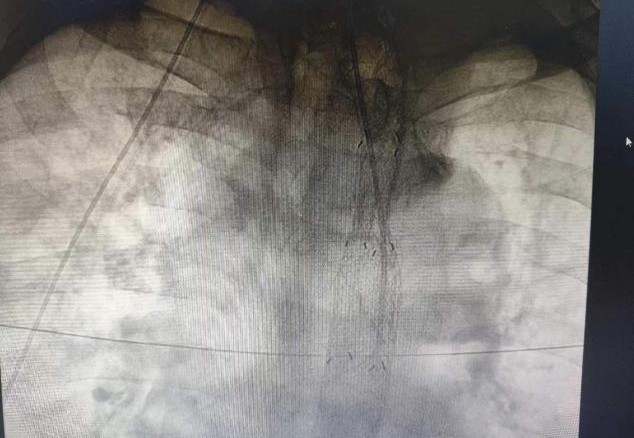

血管介入科DSA透视下食管癌光动力治疗